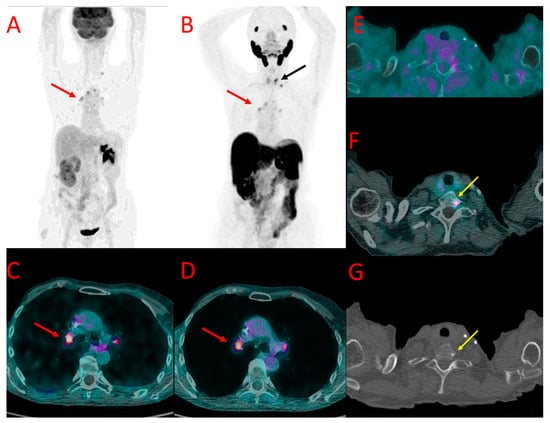

Figure 5. [18F]FDG (A) and [18F]PSMA-1007 (B) PET as well as [18F]FDG (C,E) and [18F]PSMA-1007 (D,F) PET/CT fused images of the chest (C,D) and pelvis (E,F) in patient #9. Metastatic mediastinal lymph nodes (yellow arrows at (AD)) showed uptake of both tracers, slightly higher in [18F]FDG scans (SUVmax 3.3 vs. 2.9, TBR 2.1 vs. 2.4). On the contrary, bone metastasis in the left iliac bone was detectable only with [18F]PSMA-1007 PET/CT (red arrow at (B,E,F)) with SUVmax of 6.2 and TBR 6.9, without any osteolytic lesion in the CT (E).

Altogether, bone metastases were found in five patients (#4, 5, 8, 9, and 10). PET-positive bone lesions characteristic of bone metastases were found in both PET/CT modalities in three patients (#4, 5, and 8). In all of them, the SUVmax values measured in the bone lesions were higher in PET/CT with [18F]PSMA-1007 (6.8, 9.8, 18.1) than with [18F]FDG (3.8, 5.3, 16.7, respectively), with TBR in [18F]PSMA-1007 5.7, 8.2, 15.0 and in [18F]FDG 3.2, 7.6, 11.9, respectively (Figure 2 and Figure 3E,F). The number of bone metastases ranged from one lesion visible in both methods (#5) to uncountable lesions in two remaining patients (#4, 8), However, the number of [18F]PSMA-1007-positive lesions was higher than [18F]FDG -positive metastases in patient #8 (in particular, higher detectability of [18F]PSMA-1007 PET/CT was observed in cranial bones).

In two other patients (#9 and #10), foci of increased [18F]PSMA-1007 uptake were detected in the bones that were not visible in [18F]FDG PET/CT. In patient #9, two lesions were found in the iliac bone and Th9 vertebral body (Figure 5). These lesions did not show any morphological correlation in the bone structure; in spite of that, they were interpreted as bone metastases due to their presentation, anatomical location, and relatively high SUVmax (6.2, TBR 6.9). In patient #10, a solitary focus of increased [18F]PSMA-1007 accumulation (SUVmax 7.3, TBR 6.1) was found in the Th1 vertebral body. The lesion was osteosclerotic in the CT and had a diameter of 6 mm. It did not show any [18F]FDG uptake (Figure 6).